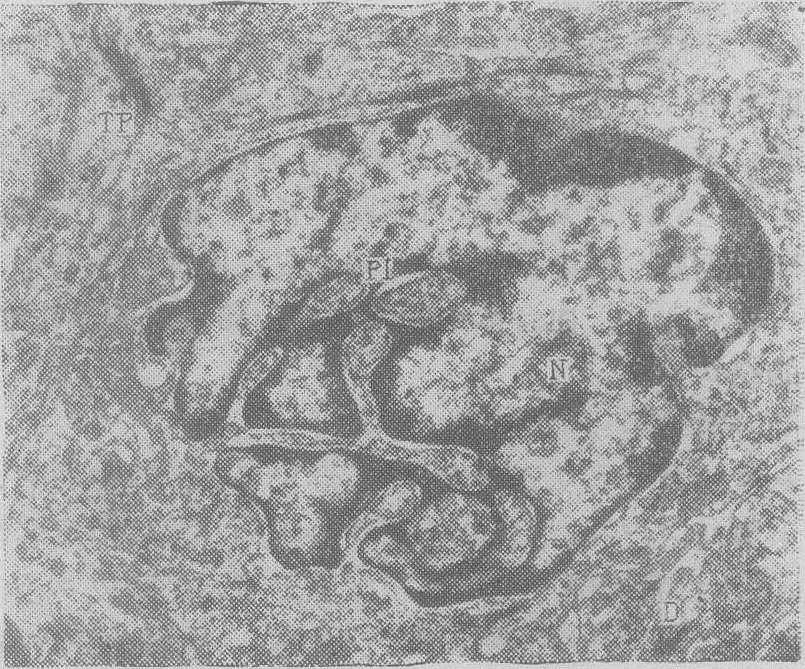

图4 鳞癌细胞。核膜凹陷明显,核(N)呈畸形,有假包涵体(PI)形成。胞浆内张力原纤维(TF),胞间有桥粒(D)×20000

(1) 分化低: 恶性肿瘤根据其分化程度大致可分为三类,即较高分化类、低分化类及未分化类。分化较高的恶性细胞,其微细结构比较接近正常的成熟细胞。例如上皮组织来源的肿瘤,细胞间常有明显的联结;鳞癌细胞的细胞间可见桥粒,细胞质内有张力原纤维(图1),腺癌细胞间可见桥粒及紧密联结,细胞质内有丰富的粗面内质网(图2),也可有分泌泡或分泌颗粒。低分化恶性细胞的超微结构尚保留一定程度类似其发生组织的分化特点,借以判断其组织来源。如低分化鳞癌中,细胞质中仍可见少量张力原纤维,细胞间有少数发育不好的桥粒;在低分化腺癌中,细胞质内泡状系统(粗面内质网及高尔基复合体)较发达,有少量分泌泡或分泌颗粒,细胞间可见少量桥粒及紧密联结或微腺腔。未分化恶性肿瘤基本失去原有组织的分化特点,细胞质内有丰富的核蛋白体,其他细胞器很少,如系从上皮组织来源的未分化癌,仅见极少的细胞间联结,且发育很差(图3)。

在同一例恶性肿瘤中,绝大部分细胞的分化程度倾向一致,但其中也有差异。在大部分分化较高的瘤细胞中,也可有少数分化较低的细胞,此类细胞数量虽少,但在浸润、转移方面常有重要的作用。反之,在大部分由未分化瘤细胞组成的瘤组织中,也可有少数分化较高的细胞,可借此判断肿瘤组织的来源。即使在同一种肿瘤细胞内的各种成分,如胞核、胞质、胞膜,或胞质内不同细胞器的分化程度也可以不同步,其中有的分化较高,有的分化较低。有些恶性肿瘤组织或细胞具有双相性分化的特性,即在同一例瘤组织内,有两种不同组织来源的瘤细胞,或在同一瘤细胞内具有两种不同组织来源的细胞分化; 其中常见的是在同一癌细胞中,既可看到鳞状上皮细胞的、又可看到腺上皮细胞的分化特点,即胞质内既有张力原纤维,又有较丰富的泡状系统和分泌泡,或细胞呈腺上皮排列并形成腺腔。在鼻咽癌、肺癌、乳腺癌、子宫颈癌、肠癌中,亦可偶见这类双相性分化特点。此外,在一些胃癌细胞中,既可见到肠上皮细胞的特点,如肠型微绒毛及粘液分泌泡,也可看到胃粘膜上皮细胞的特点,如胃型粘液泡及微绒毛。有的肿瘤组织可有上皮细胞的及间叶细胞的双相性分化的特点,例如滑膜肉瘤内有上皮样成分,其细胞间可见桥粒,还有成纤维细胞样成分;间皮瘤亦然。(2) 异型性: 恶性肿瘤有分化低的特点,但与胚胎发育过程中分化低的胚胎细胞及成熟个体中的幼稚细胞不尽相同,表现在组织与细胞结构上有不同程度的畸变,称异型性变。过去曾有人将低分化与异型性两个不同的概念混同起来。实际上,低分化肿瘤的异型性不一定大(如成视网膜细胞瘤与胚胎性视网膜相比较),而异型性显著的瘤细胞分化不一定低(如多形性鳞状上皮癌,多形性纤维肉瘤)。异形性包括组织结构的异型性与细胞异型性。前者表现在细胞排列的相互关系上,即所谓细胞的极向,恶性肿瘤组织常呈极向紊乱,此种特点在光学显微镜下容易识别;而细胞异型性包括细胞形状、大小及细胞内部结构的变化,特别是后者,只有在超微结构的检查中才易识别。异型性的核可见核膜常呈齿状曲折,有的凹陷很深,使核变成畸形。由于核膜内陷,部分细胞质随同核膜陷入核内,形成假包涵体(图4)。有的核周间隙在局部或整体有明显的扩张,核仁的形状也可显示出多样性。细胞器也可见异型性变,如线粒体分布不规则,有些区域很多,有些区域很少;形状大小也可不一,呈分枝状、线状、圈状或马蹄状。线粒体的嵴一般减少,方向亦乱。粗面内质网亦有异型性变,有的区域密集,有的区域稀少,有的排列呈同心圆状,有的呈指纹状,或有明显的扩张。细胞联结的分布亦不均匀,有的区域可以多个成串出现,有的区域很少。桥粒的长短及发育也不一致。细胞表面的微绒毛稀疏与长短可以不一,肠型微绒毛的轴丝,其细胞内部分,也可表现出方向错乱与深度不一。